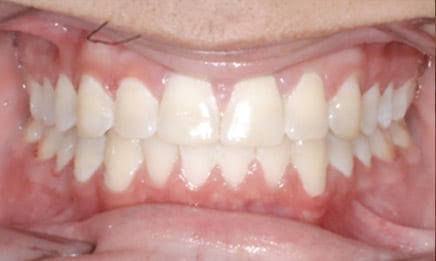

The main benefits from this treatment include improving function and appearance of the teeth and smile, moving permanent teeth into their proper positions, aligning the jaw, and preventing future problems due to poor alignment.

As you can see, there are so many different reasons for braces. Getting treated as a youth is not only much easier for the patient (socially), but the outcome will be much better as we are able to start aligning things as the body is growing.